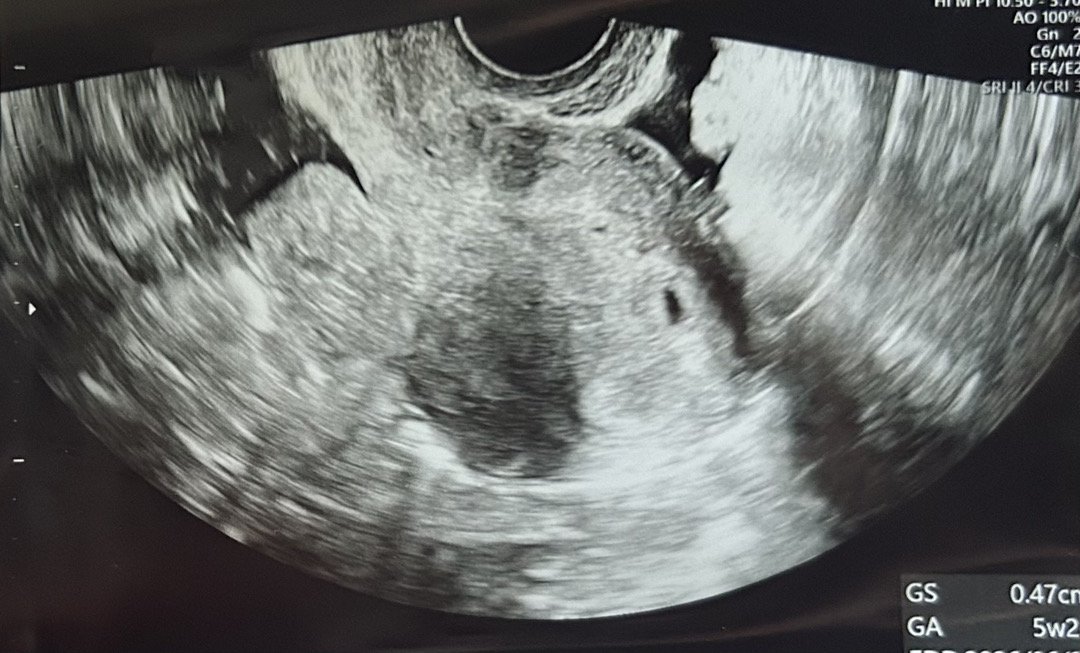

5주1일 초음파 사진 괜찮은가요?

5주1일 초음파 사진 괜찮은가요? 함께 봐주실 수 있으실까요??

소중한 아기집에 보이네요 ㅎㅎ 저두 처음엔 작았는데 다음주에가니 더 커져있고 난황도 작게보였어요 😀